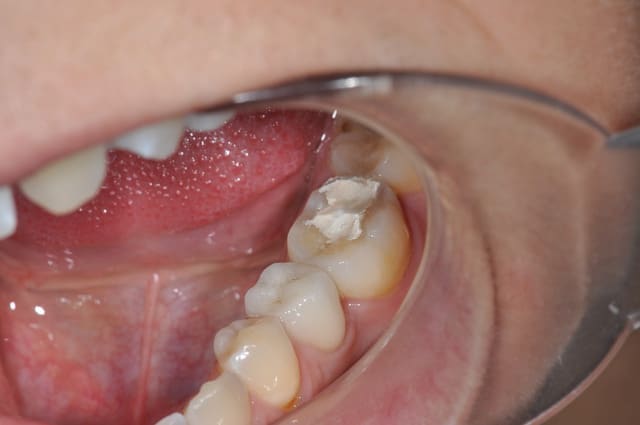

T'as pas autre chose, une photo sans le pansement, une radio, une photo des autres dents ?

Ce qui m'interpelle c'est que j'ai l'impression qu'on voit la dentine sur la face occlusale, est-ce que toutes les dents sont comme ça ?

37 semble aussi abrasée, donc je soupconne une abrasion et des parafonctions

Si t'arrives à faire ton endo sans élargir plus la chambre, c'est une indication d'Inlay.

Mais il y a fort à parier au regard de la courbure importante de la racine mésiale qu'il faudra élargir cette chambre en mésiale, à ceci s'ajoute une carie débutante toujours en mésiale (sans parler des caries multiples un peu partout), donc on se dirige à mon avis vers de la prothèse périphérique.

L'émail perdu complique un peu l'inlay-onlay.

1er choix inlay-onlay, 2e choix ccc, pas de tenon métal ou de IC.